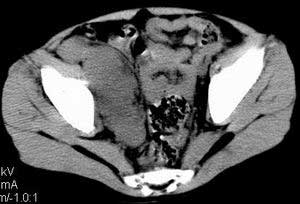

| 患者,男,9岁,因右下腹包块入院,血象不高,不规则发热,常超40度。 平扫: ![]() ![]() ![]() ![]() ![]() ![]() ![]() ![]() ![]() ![]() ![]() ![]() ![]() ![]() ![]() ![]() ![]() ![]() 增强: ![]() ![]() ![]() ![]() ![]() ![]() ![]() ![]() ![]() ![]() ![]() ![]() ![]() ![]() jiajie发言:骶椎右前区不规则软组织肿块,边缘光整,密度均匀,增强后均匀强化,右腹股沟区可见肿大淋巴结,临床有时发热,考虑淋巴瘤,儿童盆腔肿瘤应与神经母细胞瘤和横纹肌肉瘤鉴别。 longzhanghui发言:印象:盆腔右后壁不规则软组织肿块,并向前延伸.似为多个肿块融合,呈中等强化.初步考虑淋巴瘤. 听蝉观竹发言:右侧髂内、外组淋巴结肿大,从其形态和融合的情况看,同意大家意见-----考虑恶性病变,但是9岁男孩还要注意检查睾丸情况,有无隐睾? 常常类似情况是隐睾发生精原细胞瘤淋巴结转移,这个病例也要注意这一点!!! 广东凌发言:大家好,在这里我想说一下个人观点,我建议上传图片的同志能否辛苦一点就是把病史和图片都上传完整一点,比如这个病人的腹膜窗,并且这个病人的肠道的准备也是不怎么好,就从现有的质料看:病灶属于淋巴结肿大当无大的争议,有融合趋势,其内无坏死,边缘强化为主,故考虑:淋巴瘤!建议用腹膜窗看一下和肠道的关系! 阿圣发言:病灶属于淋巴结肿大当无大的争议,有融合趋势,其内无坏死,边缘强化为主,故考虑:淋巴瘤 结果是:淋巴瘤 病例来源:ct762。由宁静致远发布: http://www.radinet.com.cn/forum_view.asp?forum_id=4&view_id=2182 |